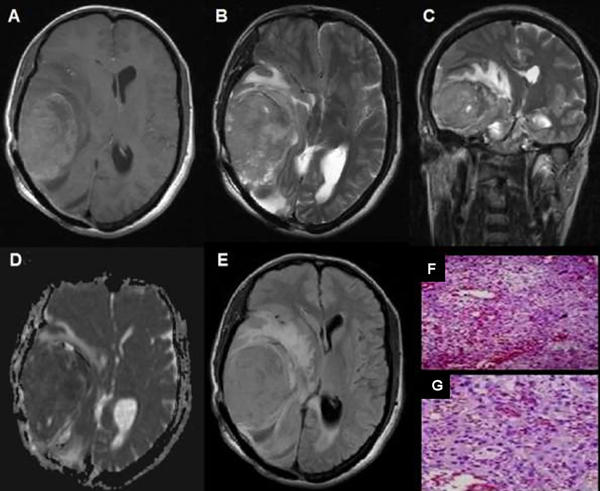

Figura 2. Meningioma de células claras, grado II OMS. (A) RM T1 axial: Meningioma parietooccipital izquierdo que produce efecto de masa (flecha). (B y C) T1 axial y sagital con Gd: Realce tenue heterogéneo (flechas). (D) Mapa de ADC: Comportamiento isointenso con aislados sectores de aumento de intensidad (flecha). (E) RM Flair axial: Efecto de masa, sin edema vasogénico (flecha). (F y G) Microscopía: Proliferación meningocelular con sectores de hipercelularidad y aumento de la tasa núcleo-citoplasma, con presencia de necrosis tumoral multifocal y sectores de atipia nuclear con nucléolos y 5 mitosis por 10 campos de aumento.

Figura 3. Meningioma rabdoide, grado III OMS. (A) RM axial T1: Meningioma temporoocipital derecho con edema perilesional significativo (flecha). (B) RM axial T2: Comportamiento heterogéneo con edema perilesional (flecha).(C) RM coronal T2: comportamiento hiperintenso con abundante edema perilesional. (D) Mapa de ADC:Comportamiento hiperintenso con disminución de intensidad (flecha). (E) RM FLAIR axial: Lesión extensa con abundante edema perilesional, (F y G) Microscopía: Meningioma con amplios sectores de diferenciación rabdoide, presencia de pleomorfismo y atipia nuclear, que alterna con sectores fusocelulares, necrosis y más de 20 mitosis por 10 campos de aumento.